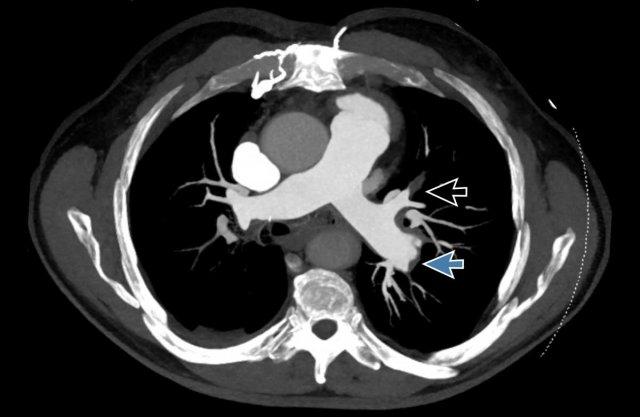

Hình ảnh

Có huyết khối phân thùy tắc nghẽn cấp tính trên nền mạn tính ở phân thùy trước của thùy trên phổi trái

(mũi tên đen).

Tắc nghẽn phân thùy có sẵn ở các nhánh đáy với hẹp đột ngột của các mạch máu ngoại vi (mũi tên xanh).

Đây là các hình ảnh của bệnh nhân nam 53 tuổi

mắc tăng áp động mạch phổi.